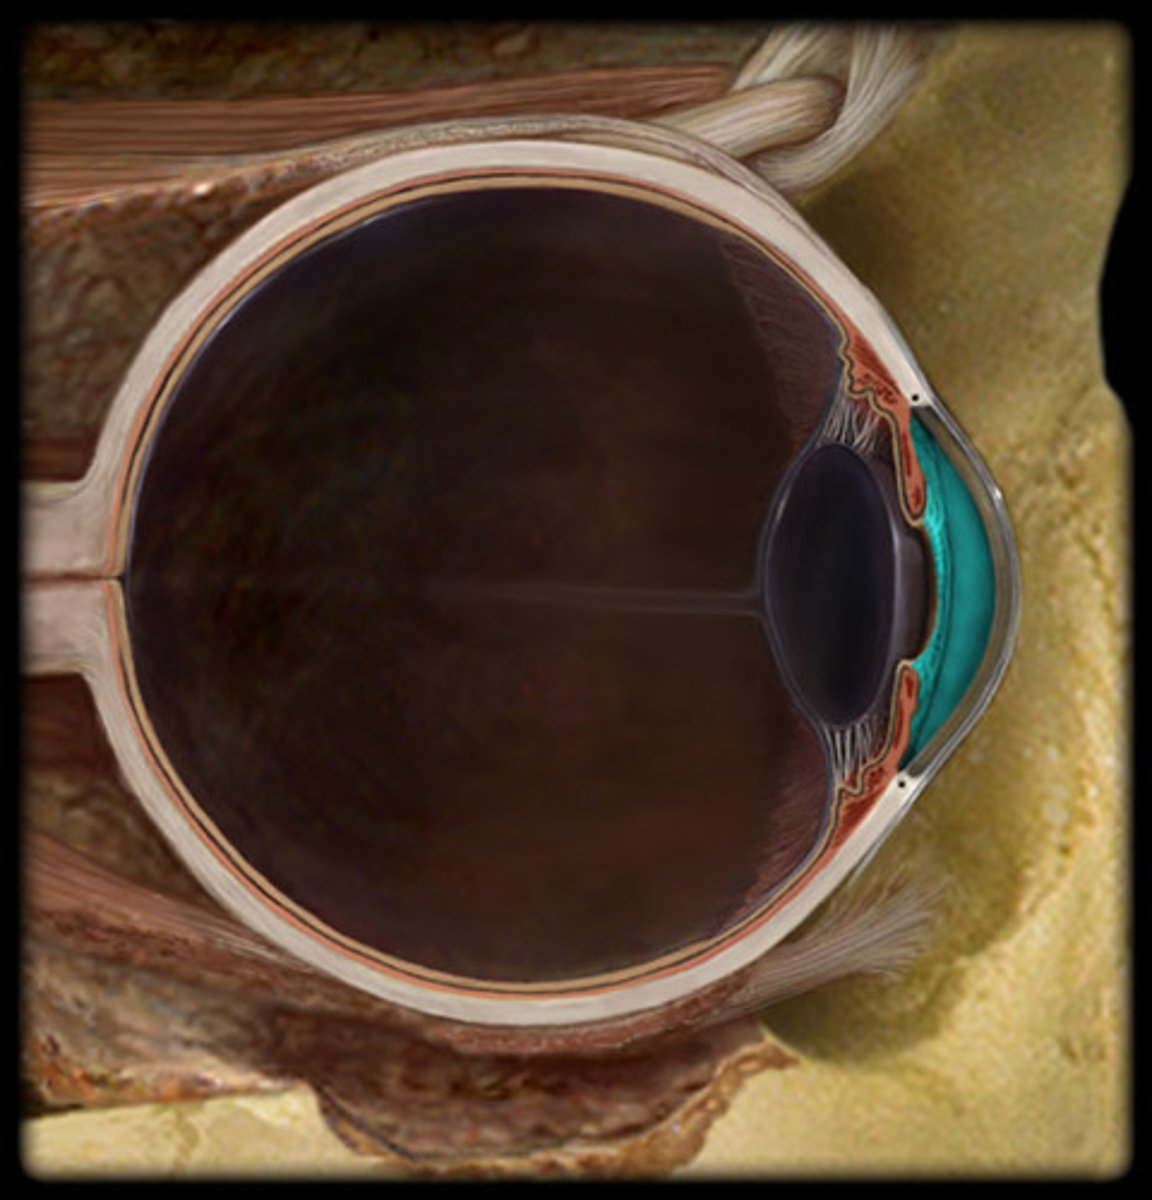

Eye

anterior chamber

posterior chamber

choroid

ciliary body

cornea

iris

lens

pupil

Sclera

suspensory ligament of eye